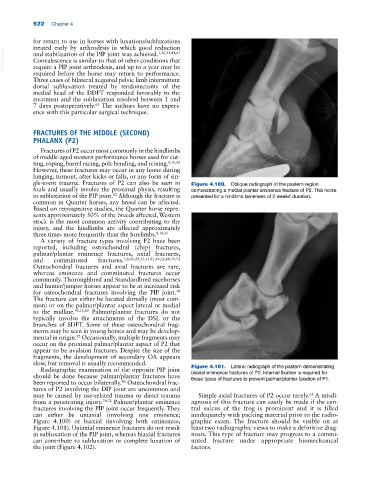

gle‐event trauma. Fractures of P2 can also be seen in Figure 4.100. Oblique radiograph of the pastern region

foals and usually involve the proximal physis, resulting demonstrating a medial plantar eminence fracture of P2. This horse

in subluxation of the PIP joint. Although the fracture is presented for a hindlimb lameness of 2 weeks’ duration.